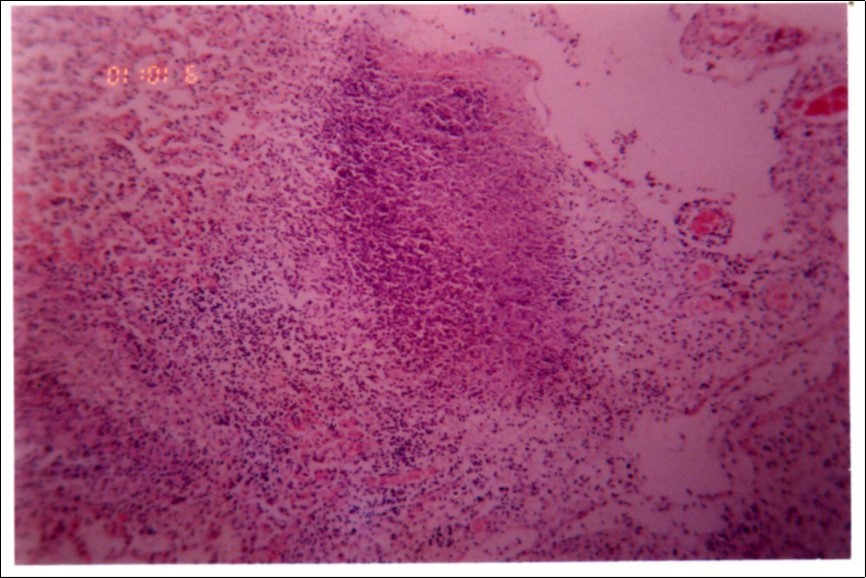

Figure 3, Figure 4 and Figure 5 show different histopathological pictures of hepatized lung tissue samples from which Mmm isolates were recovered. In Figure 3, widened interlobular septa, due to presence of fibrinous necrosis and cellular infiltration were observed. Figure 4 shows extensive loss of airspace due to necrosis and infiltration of neutrophils. Figure 5 shows hyperemia of alveolar wall capillaries and infiltration of few fibrin and neutrophils.

Figure 4.Extensive loss of air space due to necrosis and infiltration of neutrophils (H&E ×100).

Although no advanced techniques like PCR were used to identify the isolates, procedures used in this study were quite enough to confirm the incidence. Affected animals with CBPP were diagnosed based on the clinical signs, the PM findings, the typical histopathological picture in addition to the isolation of the causative agent and its subsequent identification using cultural and biochemical procedures. Identification of the isolates was confirmed by the growth inhibition test as recommended in OIE manual 10. The histopathological sections of diseased lungs, from which Mmm (SC) was isolated, showed typical histopathological picture of CBPP. The CBPP lesion comprises abronchiolar necrosis and oedema which progress rapidly to an exudative serofibrinous bronchiolitis with extension to the alveoli and uptake of alveolar fluid into tissue spaces 17, lymphatic vessels and ultimately septal lymphatics 18. With stasis, lymphatic vessels become thrombosed and ultimately fibrosed 19. The histological section of the lung in acute stage of the disease showed odema in the lymphatics of the interlobular septa and interstitial tissue and massive infiltration of fibrin, macrophage and neutrophils into the alveolar lumen 20. Also there was presence of lymphocytes and alveolar macrophages around the lymphatic vessels and septa margin 21. These findings supported the isolation results and gave additional evidence for the diagnosis of the disease.